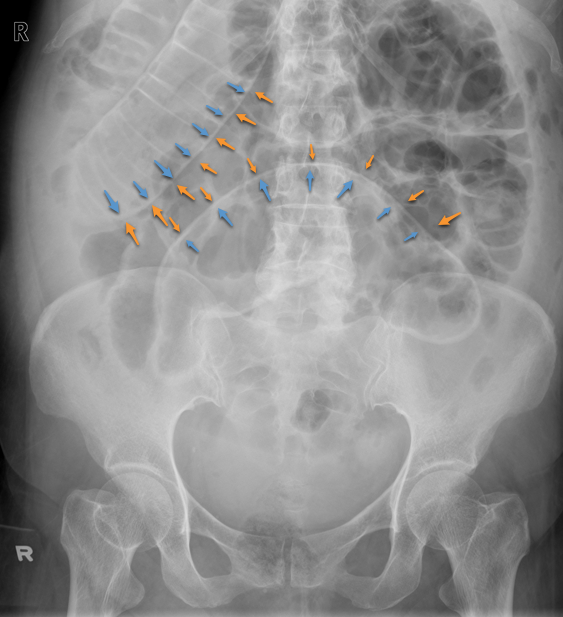

Rigler Sign (Double Bowel Wall Sign)

• Free gas/air is seen on both sides of the bowel causing the bowel wall to be very pronounced

• Indicates the presence of pneumoperitoneum